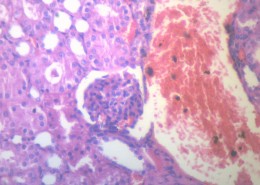

肾小管坏死(12)张

为急肾衰最常见类型,约占75%~80%.它是由于各种病因引起肾缺血及/或肾毒性损害导致肾功能急骤、进行性减退而出现的临床综合征.主要表现为肾小球滤过率明显降低所致的进行性氮质血症,以及肾小管重吸收和排泄功能低下所致的水、电解质和酸碱平衡失调.据尿量减少与否分少尿(无尿)…